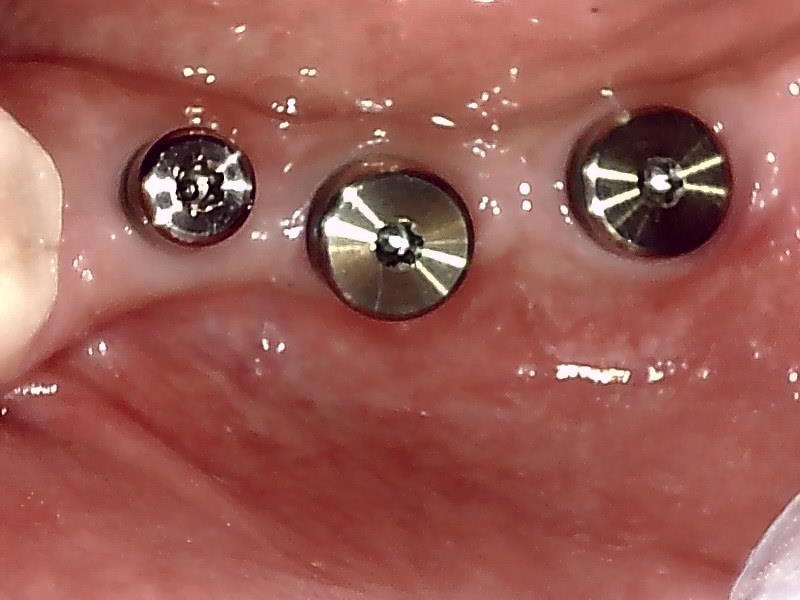

術中インプラント埋入した状態は良好です。

インプラント埋入後、10ヶ月経過した健全な顎堤の状態です。

歯肉切開してヒーリングアバットメントの装着している状況です。